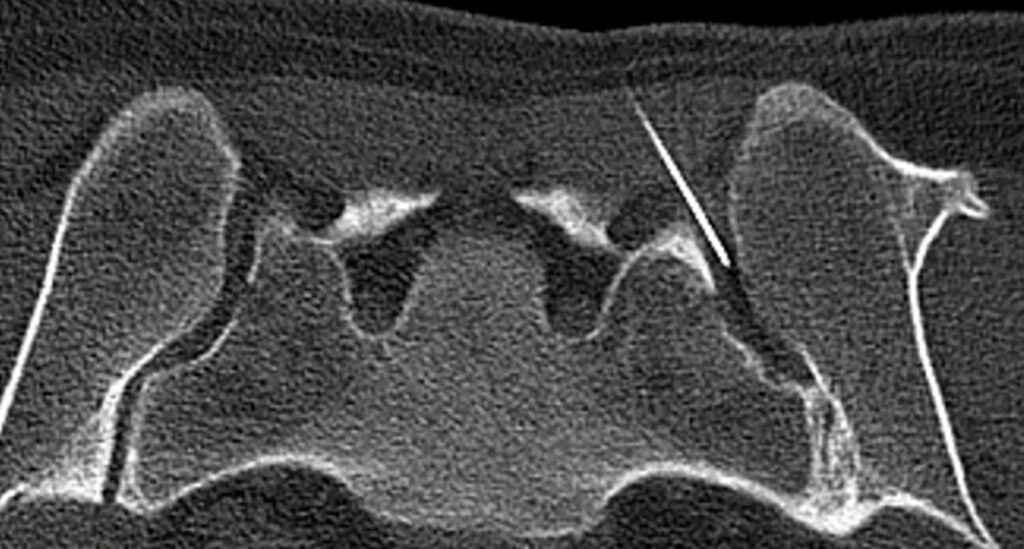

Das 0.55 Tesla MRT reduziert störende Bildverzerrungen durch Metallimplantate wie Prothesen oder Schrauben.

Das MRT eignet sich besonders gut, um frühzeitig Lockerungen von Prothesen oder Schrauben zu erkennen. Es kann feinste Veränderungen an der Knochenstruktur oder an den Implantaten nachweisen, die auf eine Lockerung hinweisen könnten.